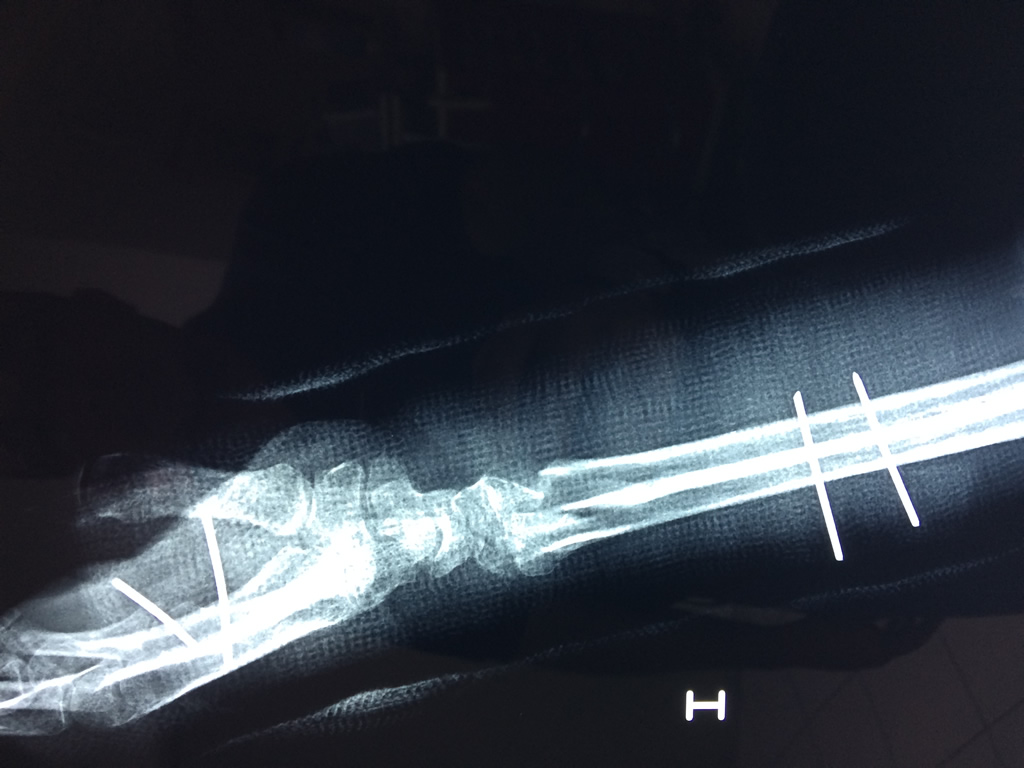

Cirugías de Codo - Cirugías de Muñecas y Manos

Los procedimientos más comunes en cirugía de la mano son aquellos destinados a reparar traumatismos, incluyendo lesiones de tendones, nervios, vasos sanguíneos, y articulaciones; huesos fracturados; y quemaduras, cortes, y otros daños de la piel.